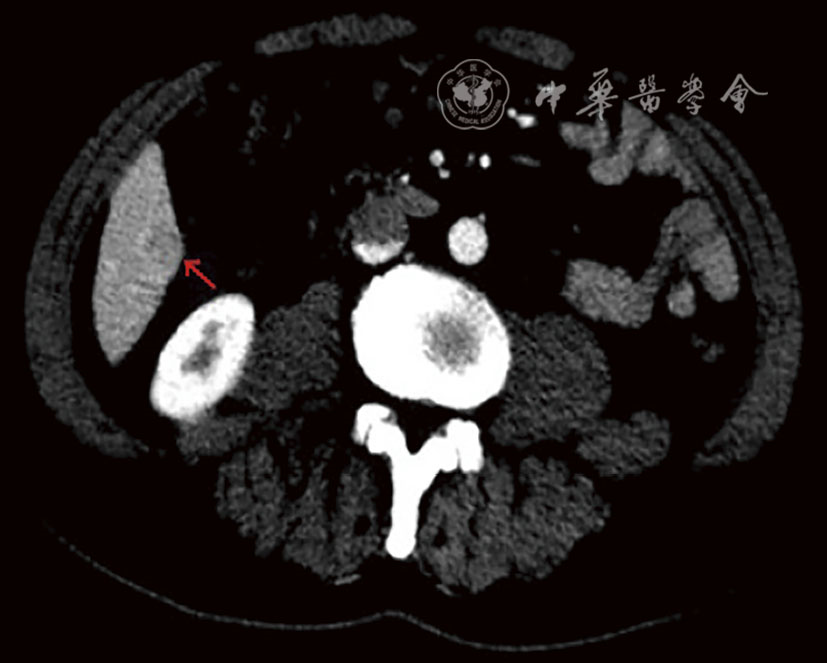

In this report, a 63-year-old male patient was admitted due to "dull pain in the right upper abdomen for 2 months". Imaging and pathological examination confirmed the diagnosis of synchronous hepatocellular carcinoma (CNLC Ⅰa stage) and duodenal papillary carcinoma (moderately-poorly differentiated adenocarcinoma complicated with signet ring cell carcinoma). The patient had a history of chronic hepatitis B. After Multidisciplinary team (MDT) consultation, laparoscopic local resection of segment 5 of the liver combined with pancreatoduodenectomy were performed to achieve R0 resection. Liver metastasis occurred 2 months after operation, and it was completely relieved after TACE, tirelizumab immunotherapy and FOLFOX4 chemotherapy. Postoperative survival time has exceeded 16 months. This case of synchronous double primary carcinoma of the liver and duodenal papilla is extremely rare, and it is likely to miss the diagnosis in clinical practice, suggesting that after the diagnosis of one type of malignant tumor, comprehensive evaluation is still needed to exclude other primary lesions. PET-CT shows important value in the early identification of such multiple primary cancers. Through multi-mode strategy of individualized comprehensive treatment and whole-course management, this patient achieved favorable tumor control effect, providing reference for clinical diagnosis and treatment of such rare cases.